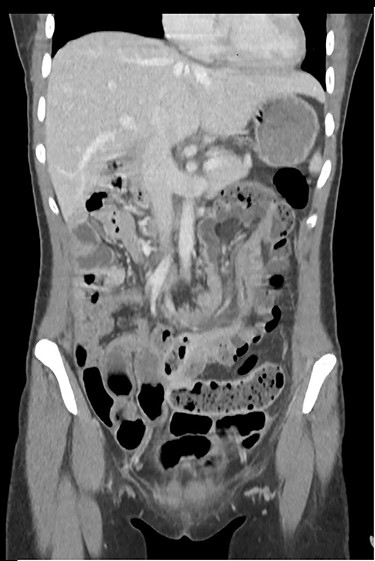

The clinical examination showed a slightly deteriorated condition and a painful distended abdomen with tenderness in all quadrants. There was no rebound pain or palpable masses. Blood tests showed a normal white cell count with a very slight elevation in C-reactive protein (7 mg/l). In the emergency department, the first diagnostic approach with ultrasonography revealed a circular concentric layer, with a maximum diameter of 4–5 cm, highly suspicious of invagination in the left upper quadrant (Fig. 1). The second step was to perform a CT scan with consequent confirmation of the diagnosis. The exam revealed a long ileocolonic intussusception of the ascending colon into the transverse colon, with possible involvement of the terminal ileum; a suspicious strangulation of a superior mesenteric artery branch was postulated (Figs 2 and 3).

CT scan with long ileocolonic intussusception of the ascending colon into the transverse colon, with possible involvement of the terminal ileum, axial plane (white arrow).